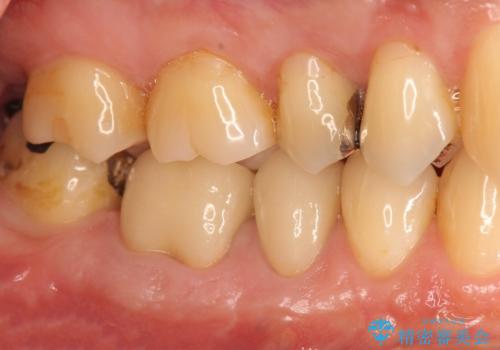

治療後、食べ物の挟まりは劇的に改善され、機能性に満足していただけると同時に見た目の審美性にも喜んでいただくことができました。